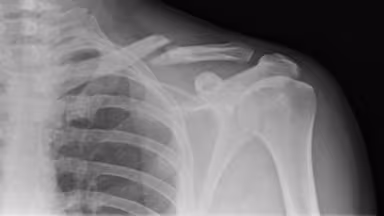

– Chụp X-quang: Đây là tiêu chuẩn vàng để xác định chính xác vị trí và loại gãy xương. Đôi khi phải chụp nhiều tư thế để đánh giá kỹ hơn mức độ di lệch.